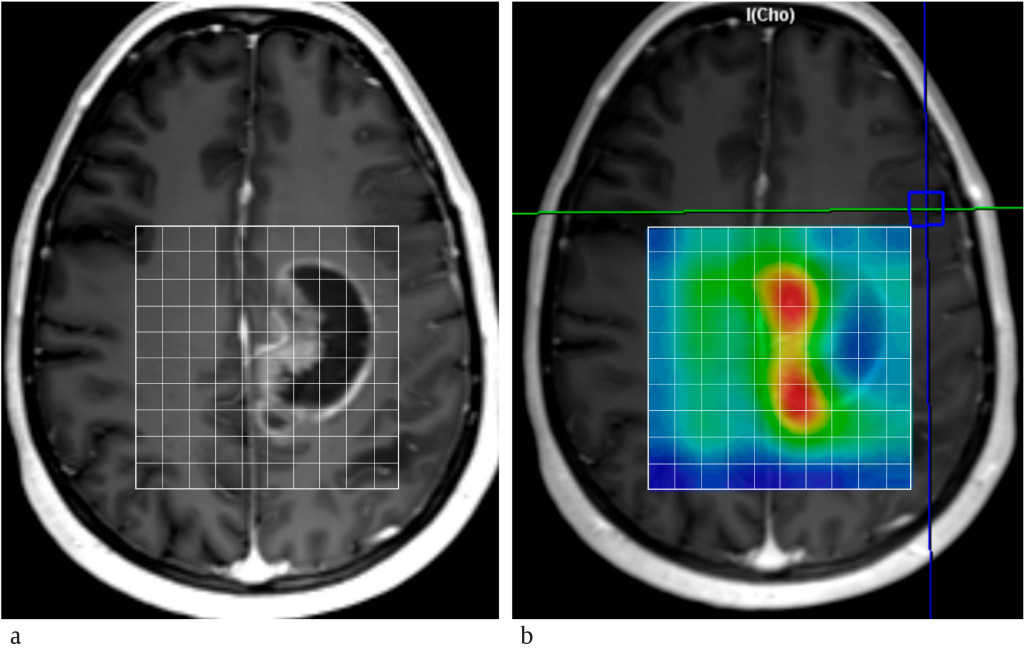

Figure 1 MR spectra from a) a patient with Leigh syndrome, b) a patient with Canavan disease and c) a healthy person, and d)…

Figure 1 MR spectra from a) a patient with Leigh syndrome, b) a patient with Canavan disease and c) a healthy person, and d) T2-weighted MRI of a patient with Canavan disease. All spectra are recorded with long echo time (135 ms). Choline (Cho), creatine (Cr), and N-acetylaspartate (NAA) appear in all spectra, and changes in these signals can often be linked to pathology. The presence of lactate can be seen in Leigh syndrome (a). In Canavan disease (b), the signal from N-acetylaspartate is far more dominant than in the spectrum from the healthy control (c). Water provides a strong signal at 4.7 ppm (parts per million) that is suppressed and outside the range shown. Spectra are scaled relative to the creatine signal.

Neurometabolic disorders are a large and heterogeneous group of congenital conditions. The incidence of each individual condition is very low, while the combined incidence is estimated to be 1 per 800–2 500 births (3, 4). Most patients with neurometabolic disorders show developmental delay or neurological signs and symptoms in the neonatal period or early childhood. Exceptionally, neurometabolic disorders may also have adult onset. Many neurometabolic disorders give rise to non-specific structural changes in the central nervous system that can be characterised with MRI, but it can be difficult to make a definitive diagnosis on the basis of imaging alone. The ability to describe the metabolite composition of brain tissue therefore makes MR spectroscopy useful in certain neurometabolic disorders. A small number of diseases have an entirely disease-specific profile on MR spectroscopy (5), while others have an MR spectroscopy profile that is specific for the condition when viewed in combination with imaging and results from clinical testing (2). Common changes in pathological MR spectra are reduced levels of N-acetylaspartate, decreased or increased levels of choline, increased levels of myo-inositol, and the presence of lactate. Examples of neurometabolic disorders that can be characterised with the aid of MR spectroscopy are mitochondrial diseases and enzyme defects (Figures 1a and 1b).

Enzyme defects may lead to failure of cellular processes if a specific enzyme is deficient or defective. Disease severity depends on which enzyme is defective, and diseases in this group have a highly variable clinical picture. Canavan disease is a leukodystrophy, in which white matter becomes oedematous and fluid-filled cavities are formed (Figure 1d). Patients with Canavan disease have specific gene mutations that lead to deficiency of the enzyme aspartoacylase, which is essential for cleavage of N-acetylaspartate into aspartate and acetate. The enzyme deficiency leads to accumulation of N-acetylaspartate in the brain and impaired myelin synthesis. The most common form of the disease has onset at six months of age and causes extensive neurological impairment (6). Signs of the disease are irritability, hypotonia and poor upper body control. The disease greatly impairs the child's development, and can give rise to increased head circumference, poor oculomotor control, blindness, epilepsy, muscle stiffness and spasms. Life expectancy is about ten years. MR spectroscopy of patients with Canavan disease shows a strongly elevated N-acetylaspartate signal (Figure 1b). Canavan disease is the only known metabolic disorder to cause an increase in N-acetylaspartate levels.

Mitochondrial diseases are a heterogeneous group of disorders that give rise to progressive or intermittent brain damage (7). MRI shows varying findings with oedema and tissue loss, but bilateral involvement of the basal ganglia is typical. Together with MRI and clinical findings, MR spectroscopy can help identify and characterise mitochondrial diseases. The most common finding on MR spectroscopy is the presence of lactate owing to altered intracellular energy production, often followed by decreased N-acetylaspartate, which indicates cell loss. Leigh syndrome is a mitochondriopathy that can cause developmental delay, spasticity and brainstem dysfunction. MRI typically shows symmetrical signal changes in the basal ganglia, thalamus and brainstem. Lactate in MR spectra from these areas strengthens suspicion of Leigh syndrome (Figure 1a).